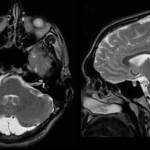

Термин «ретроцеребеллярная» – это не характеристика самой кисты, а указание на ее расположение за мозжечком (cerebellum), в области задней черепной ямки, что показывают данные МРТ, посредством которой эти самые кисты и выявляются.

пример кистозного расширения ретроцеребеллярного арахноидального пространства